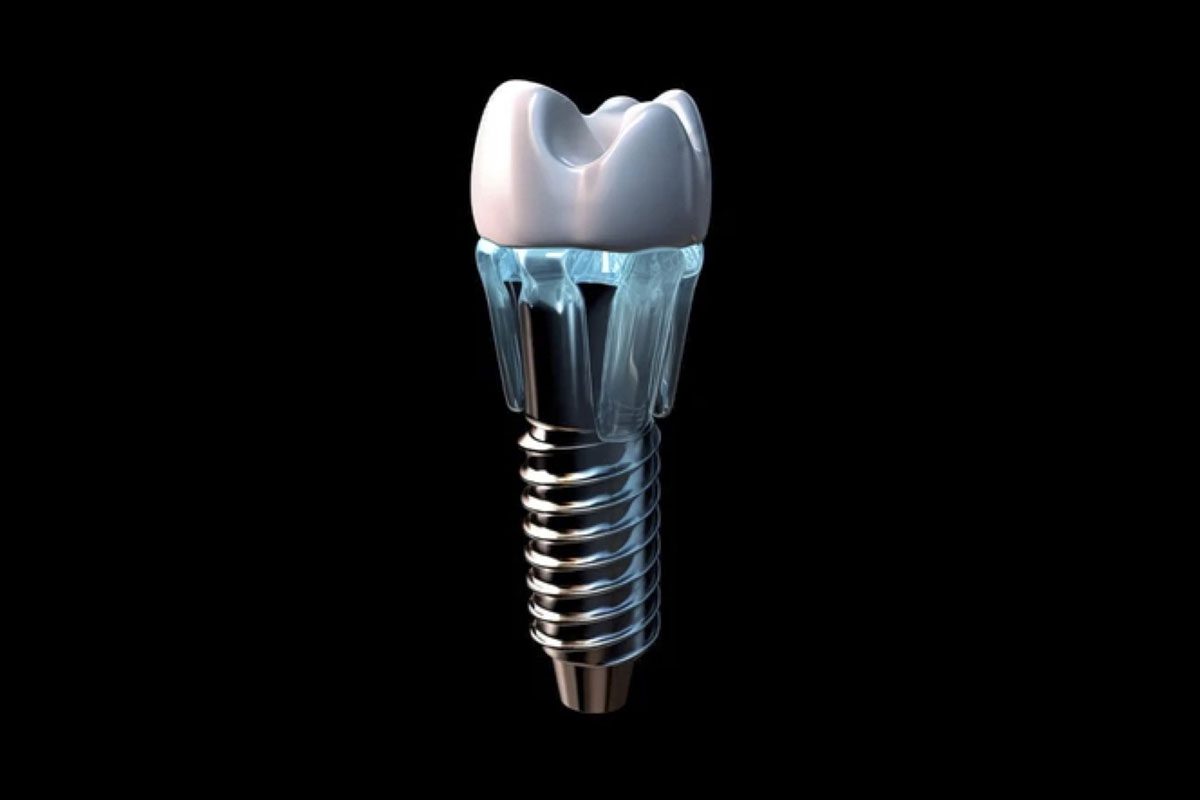

Implants

Dental implants are the ideal solution to replace missing or severely damaged teeth. Minimally invasive procedure, natural looking and long-lasting.